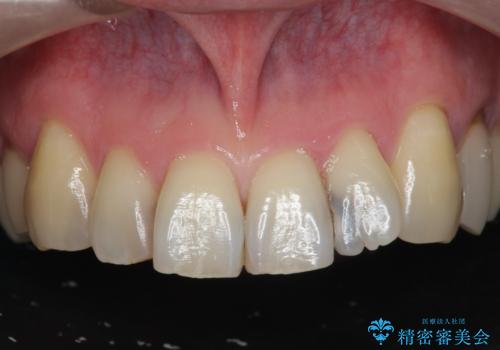

[ セラミック治療 ] 前歯の見た目を改善したい

担当医 大元洋佑

![[ セラミック治療 ] 前歯の見た目を改善したいの症例 治療前](https://seimitsushinbi.jp/wp/wp-content/uploads/2025/10/IMG_9990-2-500x350.jpg?v=1761816440)

![[ セラミック治療 ] 前歯の見た目を改善したいの症例 治療後](https://seimitsushinbi.jp/wp/wp-content/uploads/2025/10/IMG_9934-500x350.jpg?v=1761816431)